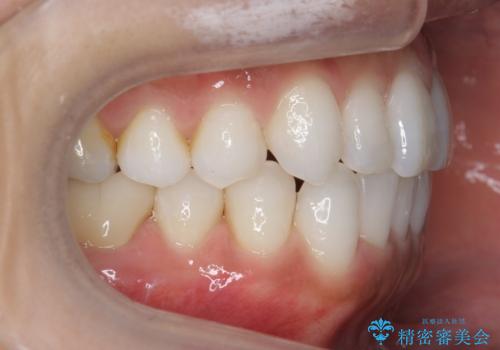

30代女性 前歯のがたつき

- 30代女性

- 矯正装置

- インビザライン

- 治療期間

- 1年5ヶ月

- 前歯のがたつきを主訴に来院。

右下の奥の銀歯も治療しています。

下の前歯を下げるため、IPR(歯をわずかに削る処置)を行っています。